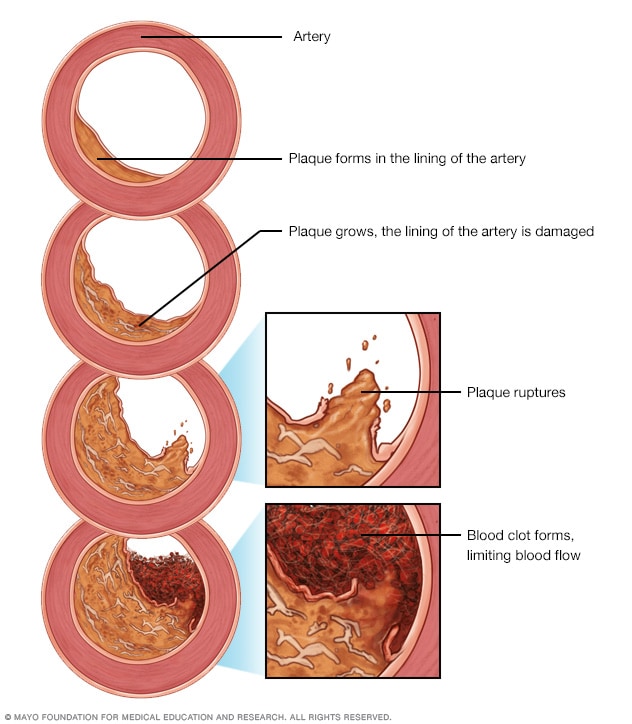

Arteriosclerosis / atherosclerosis – Symptoms and causes – Mayo Clinic

Different stages in progression of atherosclerosis [8]. | Download …

| Progressive atherosclerotic lesions. Pathological intima thickening …